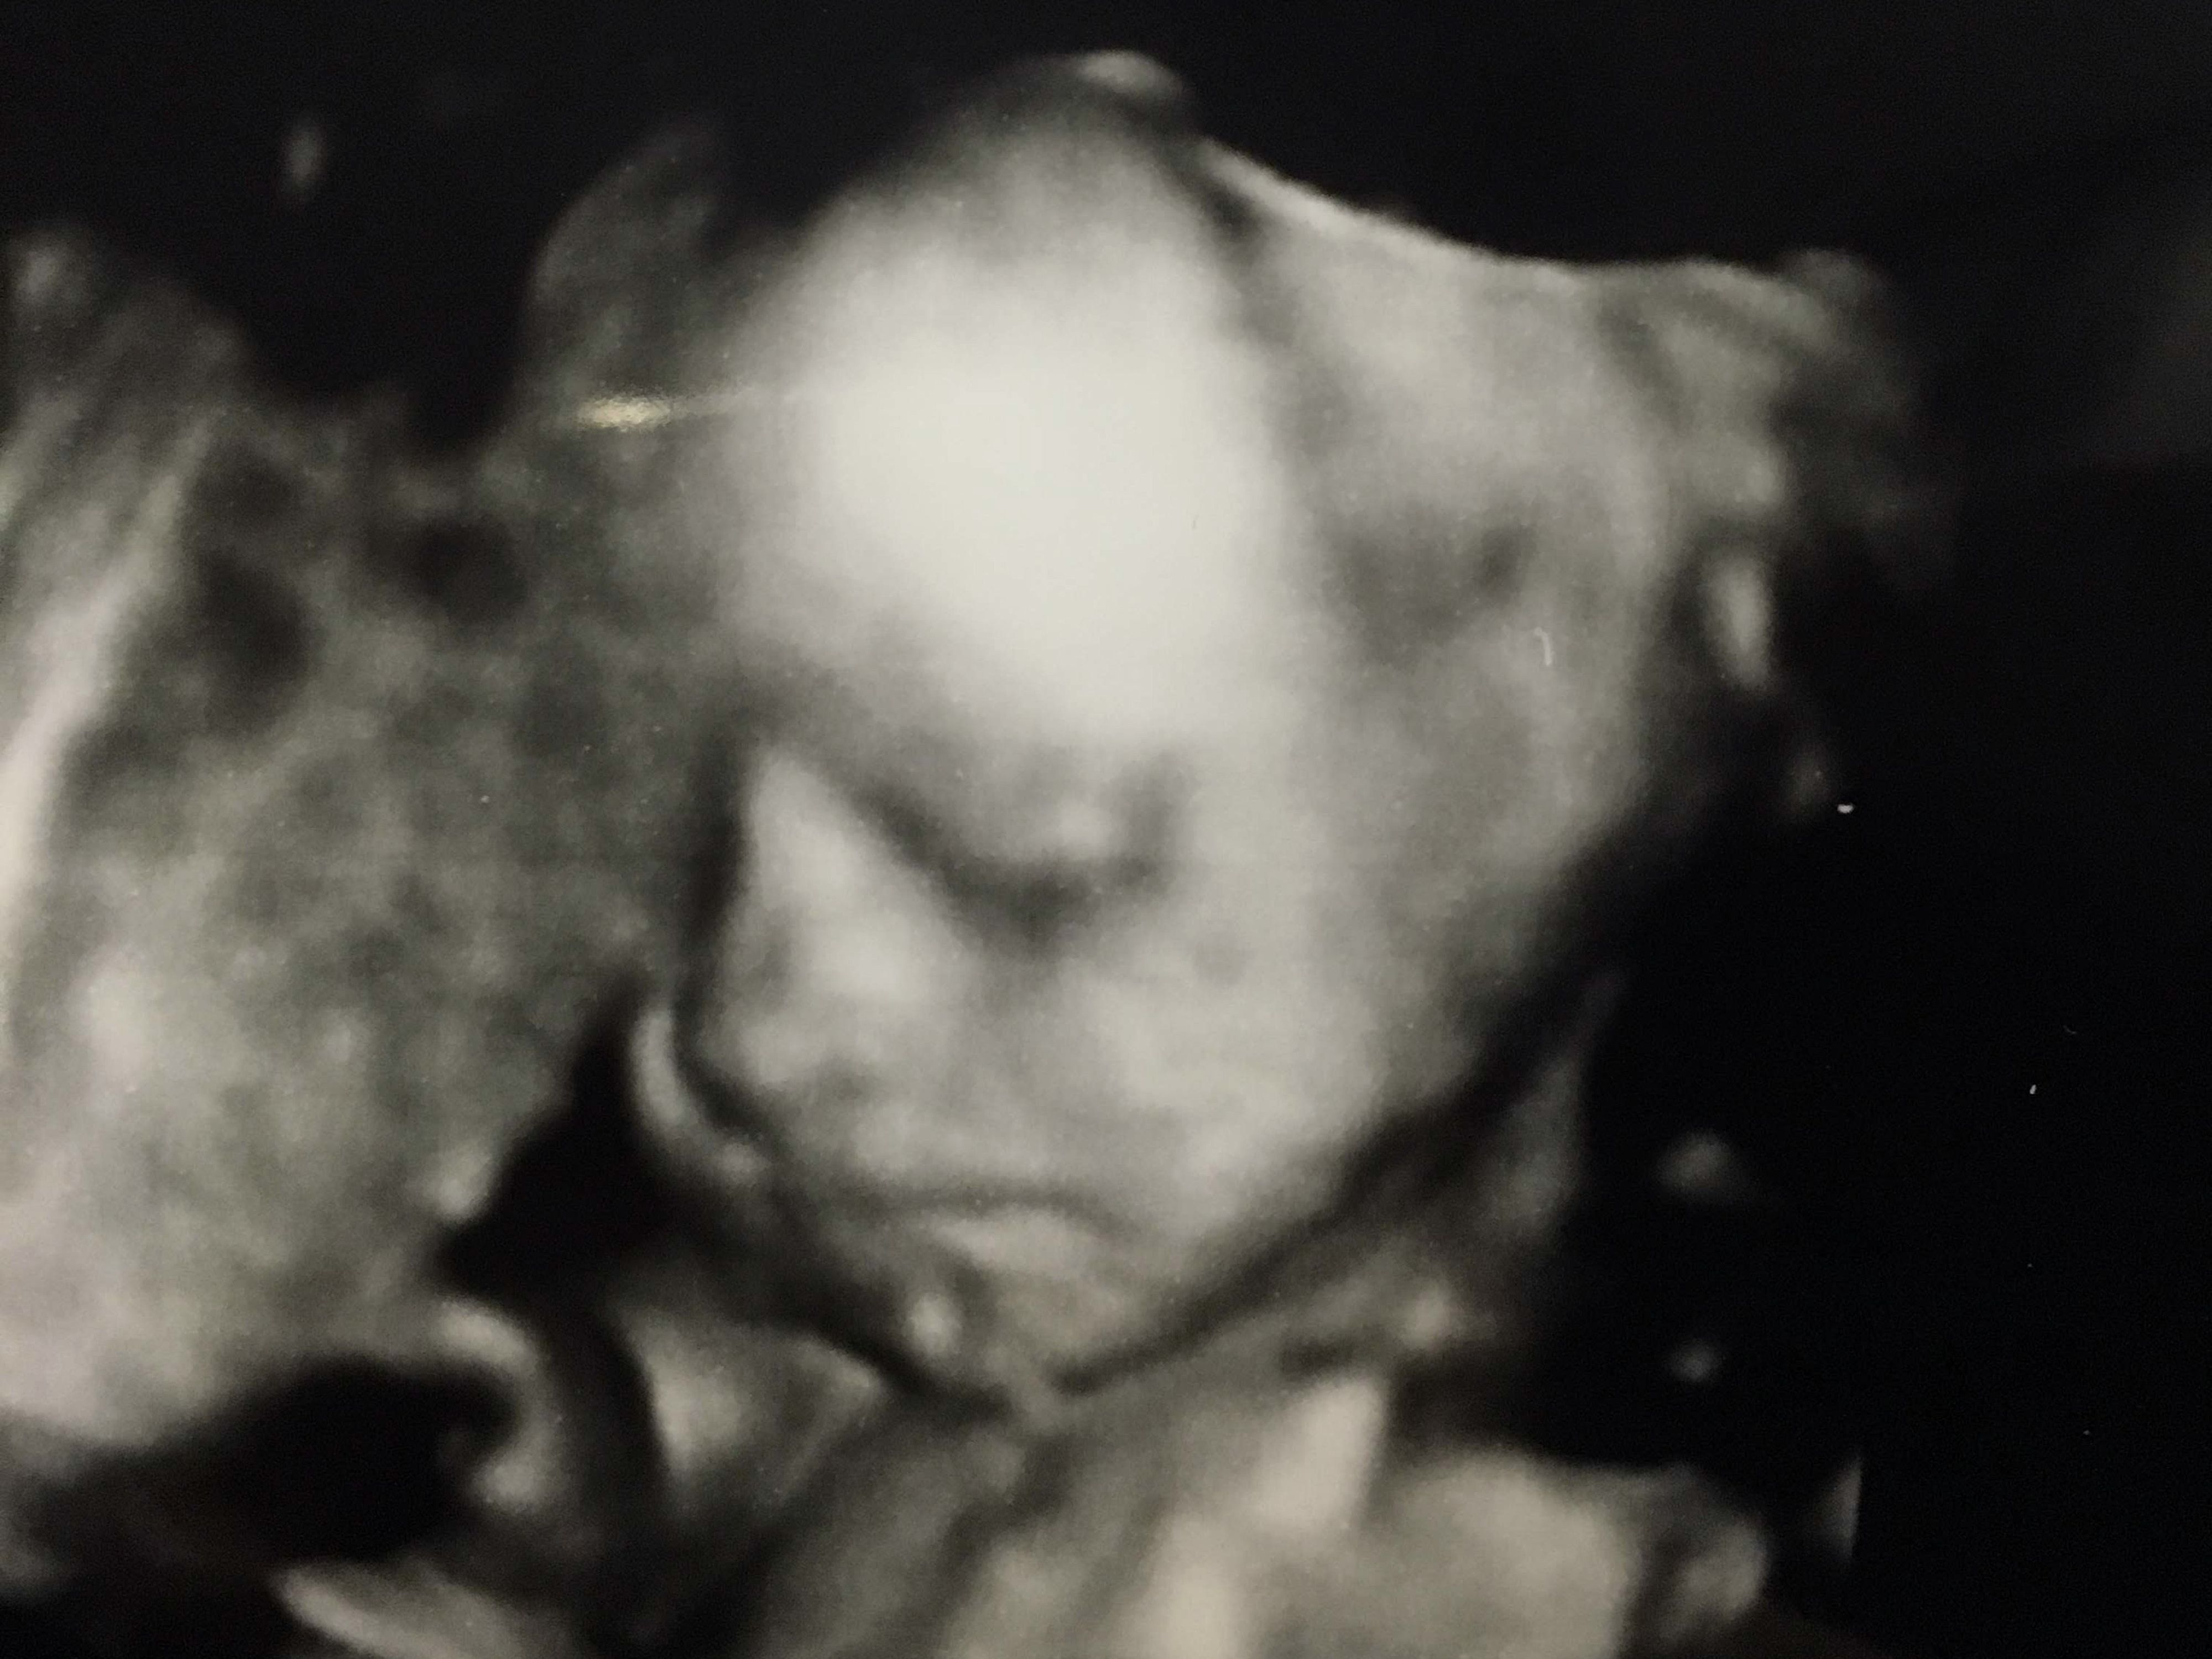

妊娠23週目 4Dエコーで、かわいい顔が!

4Dエコーできれいに赤ちゃんの顔が撮れた時の写真です。写真中央に大きく顔が写り、目・鼻・口がはっきりと見えます。予想以上にしっかりと表情が見えたので驚きました。鼻が私にそっくりで、とても嬉しかったです。

また、このエコー写真を両親にも見せたところ、初孫を楽しみにしていた父は「かわいい!」と大喜び。夫は「こんなにきれいに見えるものなのか」と驚いていました。